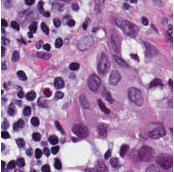

Pathology slides contain abundant phenotypic information, and are widely used to study the manifestations of disease by analyzing cells or tissues under the microscope by pathologists [1]. Nuclei segmentation is a crucial step in pathology image analysis. The shape, size, density, and other indicators of the nucleus are related to the diagnosis and treatment of cancer [2, 3]. Different staining methods are used to increase the contrast between the different structures for their visual examination, where the most commonly used staining method for nuclei analysis is hematoxylin-eosin (H&E) staining, in which nuclei are stained blue-purple by hematoxylin (H-component), and cytoplasm and stromal matrix are stained red-pink by eosin (E-component) [4, 5], as shown in Fig. 1. Besides, with the advent of dedicated scanners, slices can be easily converted to digital pathology images, which are convenient to store on computers for further processing and analysis. Therefore, the wide availability of digital H&E stained pathology images greatly facilitates researchers in developing and validating advanced automatic pathological image analysis methods with nuclei segmentation.

Point annotation can be viewed as the most efficient manner for annotation, gaining increasing attention in cell/nuclei segmentation. Existing methods [23, 24, 25, 26] mainly encode the point annotation into coarse pixel-level labels, such as point distance maps [23], Voronoi labels [24], cluster labels [25], and pseudo edge maps [26]. As shown in Fig. 1, these methods typically inject the shape and texture prior knowledge of nuclei into coarse pixel-level label. For example, the points are assumed to be around the center and the nuclei shapes are nearly convex. Despite drastically reducing the annotation cost and alleviating the data-imbalance problem of point annotation, these methods still suffer from incomplete coarse labels and inaccurate boundary information, as illustrated in Fig. 1. Various methods have been proposed to eliminate the distraction induced by the coarse labels, which can be categorized into two classes: 1) multi-stage optimization to refine the segmentation in a bootstrapping way [23, 27, 24]; 2) adding additional constraints based on the local contrast between nuclei and their surrounding cytoplasm [25, 26]. However, the additional constraints could introduce inaccurate supervision, and a multi-stage learning strategy may suffer from error accumulation (i.e., the global optimum cannot be guaranteed).

In practice, directly using point annotation for the nuclei segmentation could suffer from the data-imbalance problem due to insufficient supervision information. To alleviate this issue, we adopt the Voronoi diagram [24] and the -means clustering method [25] to generate Voronoi label and cluster label, respectively. Specifically, for Voronoi labels, as shown in Fig. 1, the image is divided into convex polygons based on the point annotations with the assumptions that the point labels are at the nuclei centers and nuclear shapes are convex (even though these assumptions are not necessarily valid). For cluster labels, as shown in Fig. 1, we utilize the -means to obtain more supervision information of nuclei boundary and shape as follows. First, we calculate the distance maps from the point labels by performing distance transform between each pair of points. Second, the distance maps are combined with the original H&E stained images to conduct the -means clustering to divide all pixels into clusters: nuclei, background, and ignored area. The clusters that have maximum and minimum overlap with the point annotations are labeled as nuclei and background, respectively. The remaining one is the ignored class. The introduction of an ignored area allows pixels that cannot be easily determined as nuclei or background with certainty not be forced into either class, ensuring that the clustering can assign correct pixel labels as much as possible [27]. Third, several morphological operations are adopted to refine the cluster label, including connected domain labeling, scattered region removing, morphological opening operation, and binary hole filling.

As shown in Fig. 1, although part of the color information is lost in the obtained H-component image, the color contrast between the nuclear and non-nuclear regions is enhanced.

where and denote the Voronoi label and cluster label of nuclei at the -th pixel, respectively; denotes the prediction of the segmentation network with H-component as input; and (i.e., or ) is the set of non-ignored pixels. As illustrated in Fig. 1, the Voronoi label is used to supervise the network to separate overlapping nuclei, while the cluster label could provide coarse shape and boundary information for nuclei segmentation. In the following, we elaborate the co-training strategy to further provide supervision to the ignored area of the coarse cluster labels, denoted with the blue color in Fig. 1.

where is the -th pixel of the pseudo label, is the set of all pixels, and denotes the predictions of with respect to the H-component . With the training set split into two non-overlapping subsets and , two segmentation networks are trained with the coarse labels (i.e., the Voronoi and cluster labels) by and , respectively, the two networks could transfer knowledge to each other with their respective pseudo labels, so as to compensate for the missing supervision information. However, the segmentation performance may still suffer from the inaccurate cluster label, as shown in Fig. 1. Hence, our next step is to explore an auxiliary colorization task that transforms H-component images back into the original H&E stained images from which more precise nuclei boundaries can be obtained.

To investigate the impact of the proposed co-training and colorization methods, we validate the effectiveness of each module on the MoNuSeg dataset. Considering that Voronoi labels provide more shape supervision information than point annotation, we regard the model that jointly uses the point annotation and the Voronoi label as the baseline, and mainly evaluate the improvement of each module upon this baseline in Table III. Model A utilizes only point annotation and Voronoi labels with cross-entropy loss. For a fair comparison with co-training, we employ two separate models which have the same architectures for co-training and average the predictions of the two models in inference. Model B further adopts the cluster label. It can be seen that the cluster loss is beneficial in segmenting overlapping nuclei, improving the from 60.20% to 72.48% and the AJI from 43.01% to 51.77%, which indicates that simply using the point annotation and the derived Voronoi labels cannot provide sufficient supervision for the nuclei segmentation due to the lack of boundary and area information. However, the cluster labels generated by the -means algorithm cannot separate close nuclei which would introduce distraction to the training process, as shown in Fig. 1. To address this challenge, Model C utilizes the co-training strategy that the two models facilitate each other in a bootstrapping way to eliminate the distraction brought by the cluster labels. As expected, co-training brings a consistent improvement in all metrics, including an 1.19% increase to AJI. We believe that co-training compensates for the loss of supervision information in the uncertain regions in the cluster label, and the probability map with EMA by another model provides more precise and robust supervision in the nuclei boundary. Visualization of the segmentation results can be found in Fig. 3, and it can be seen that with the co-training strategy, the model can achieve more accurate results, especially in the nuclei boundary area. Model D involves colorization as a proxy task to implicitly learn to be self-aware of the nuclei boundary. Instead of directly coloring the H-component (Fig. 4(a)) to the H&E map (Fig. 4(d)), we use the segmentation probability map (Fig. 4(b)) as the input of the colorization network, which can help us to boost the segmentation accuracy. The experimental result shows that integrating the colorization tasks could not only improve the by 1.54% and AJI by 3.24%, but also promote Acc by 0.18% without dropping F1 score, proving that the colorization task has a significant guiding effect on nuclei segmentation. In Fig. 4(c), the improvement of colorization in the nuclei boundary area can also be observed. In general, the four modules used in our method have complementary advantages. By minimizing the weighted sum of the four losses, the proposed framework can distinguish between nuclear and non-nuclear to the greatest extent.